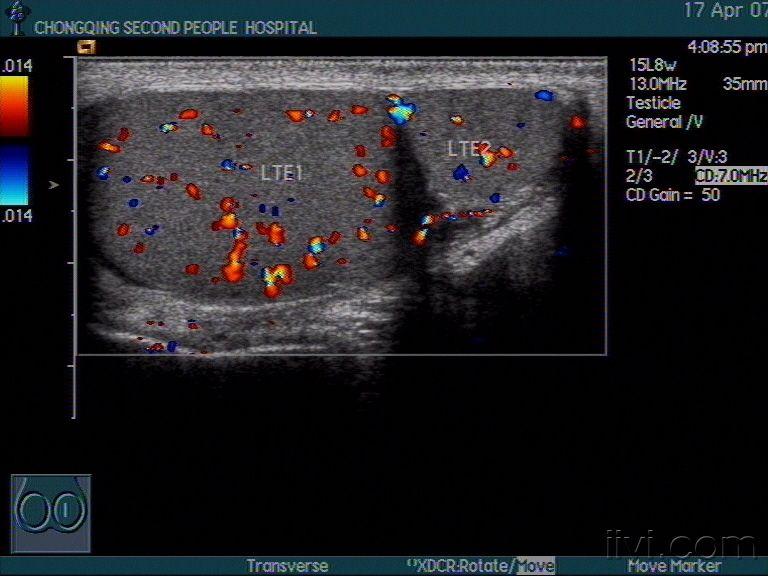

阴囊多睾症声像图

图片尺寸768x576

十万火急病例请你会诊!(随访结果在27楼--多睾症)

高频超声诊断双侧多睾症1例

图片尺寸1517x2179